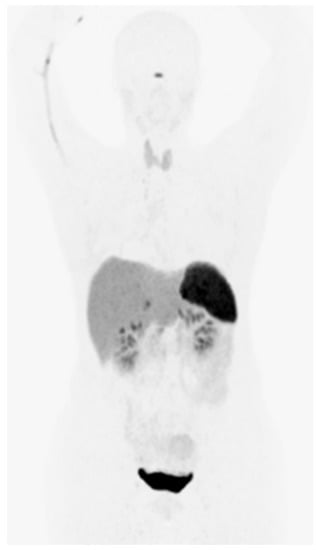

| Sonmezoglu, K. (2017) | [71] | Prospective | 21 | [68Ga]Ga-DOTA-TATE PET/CT (Siemens Biograph 6 or GE Discovery V710), 100–150 MBq, 45–60 min. [18F]FDG | No significant difference was found between the two modalities in terms of lesion numbers detected in multiple myoma. However, diffuse bone marrow uptake of DOTATATE seems to be a predicting factor for overall survival. |

4.3.1. Multiple Myeloma (MM)